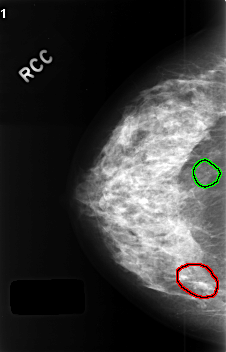

C_0407_1.RIGHT_CC

FILE: C_0407_1.RIGHT_CC.OVERLAY

TOTAL_ABNORMALITIES 2

ABNORMALITY 1

LESION_TYPE CALCIFICATION TYPE AMORPHOUS DISTRIBUTION CLUSTERED

ASSESSMENT 4

SUBTLETY 3

PATHOLOGY BENIGN

TOTAL_OUTLINES 1

BOUNDARY

ABNORMALITY 2

LESION_TYPE CALCIFICATION TYPE PLEOMORPHIC DISTRIBUTION SEGMENTAL

ASSESSMENT 3